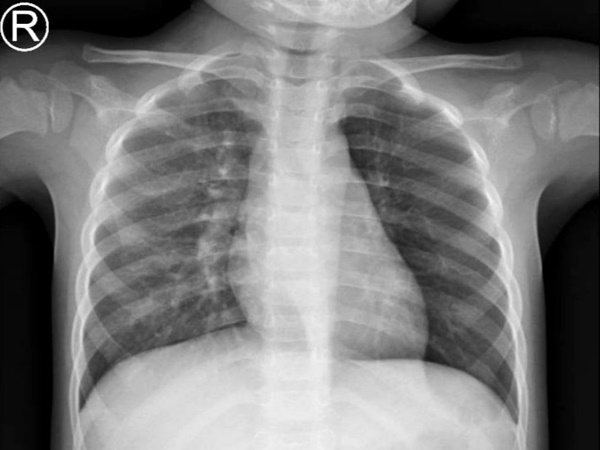

Thấy bé ngày càng khó thở sau một thời gian dài điều trị kháng sinh, xông thuốc nhiều nơi, gia đình bé đến Bệnh Viện Nhi Đồng Thành Phố. Kết quả chụp X-quang phổi thẳng dù không phát hiện dị vật nhưng có dấu hiệu ứ khí khu trú phổi trái trên phim.

Hình ảnh dị vật trên phim X-Quang.